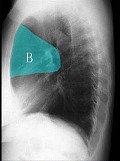

- 单项选择题如图所示正常胸部X线影像图像上,该英文字母所代表的肺段为 ( )

A、尖段

B、后段

C、尖后段

D、舌叶上段

E、前段

- E